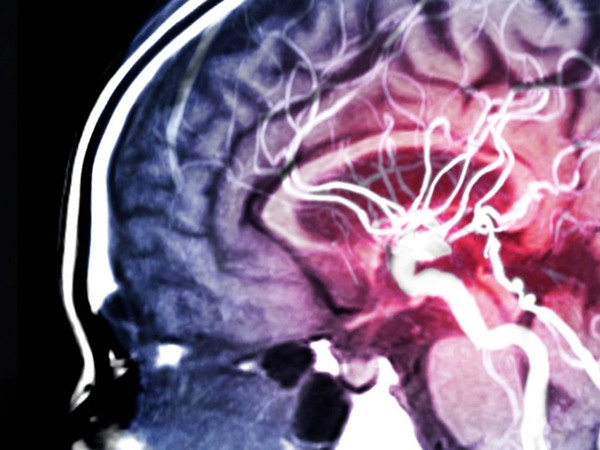

Đối với hầu hết những người trẻ tuổi, thì nguy cơ bị đột quỵ dường như là chuyện… không thực tế. Nhưng thực tế chính là thế này đây: Không có khái niệm nào gọi là “còn trẻ nên không thể bị đột quỵ” cả.

Đúng là nguy cơ bị đột quỵ tăng lên theo lứa tuổi, nhưng đột quỵ không phải là điều mà chỉ những người ở tuổi ông bà chúng ta mới gặp phải. Đột quỵ vẫn xảy ra ở những người trẻ tuổi - thậm chí là trẻ sơ sinh, trẻ nhỏ, thanh thiếu niên. Thực tế, có 10 - 15% cơn đột quỵ xảy ra ở những người khoảng 18 tuổi trở lên, chưa hề già, theo một nghiên cứu vào năm 2020 của tạp chí Stroke.

Có một điều trớ trêu là, trong khi tỷ lệ đột quỵ nói chung đang giảm đi, đặc biệt là ở người trên 65 tuổi, thì tỷ lệ này lại đang tăng lên ở người trẻ tuổi.